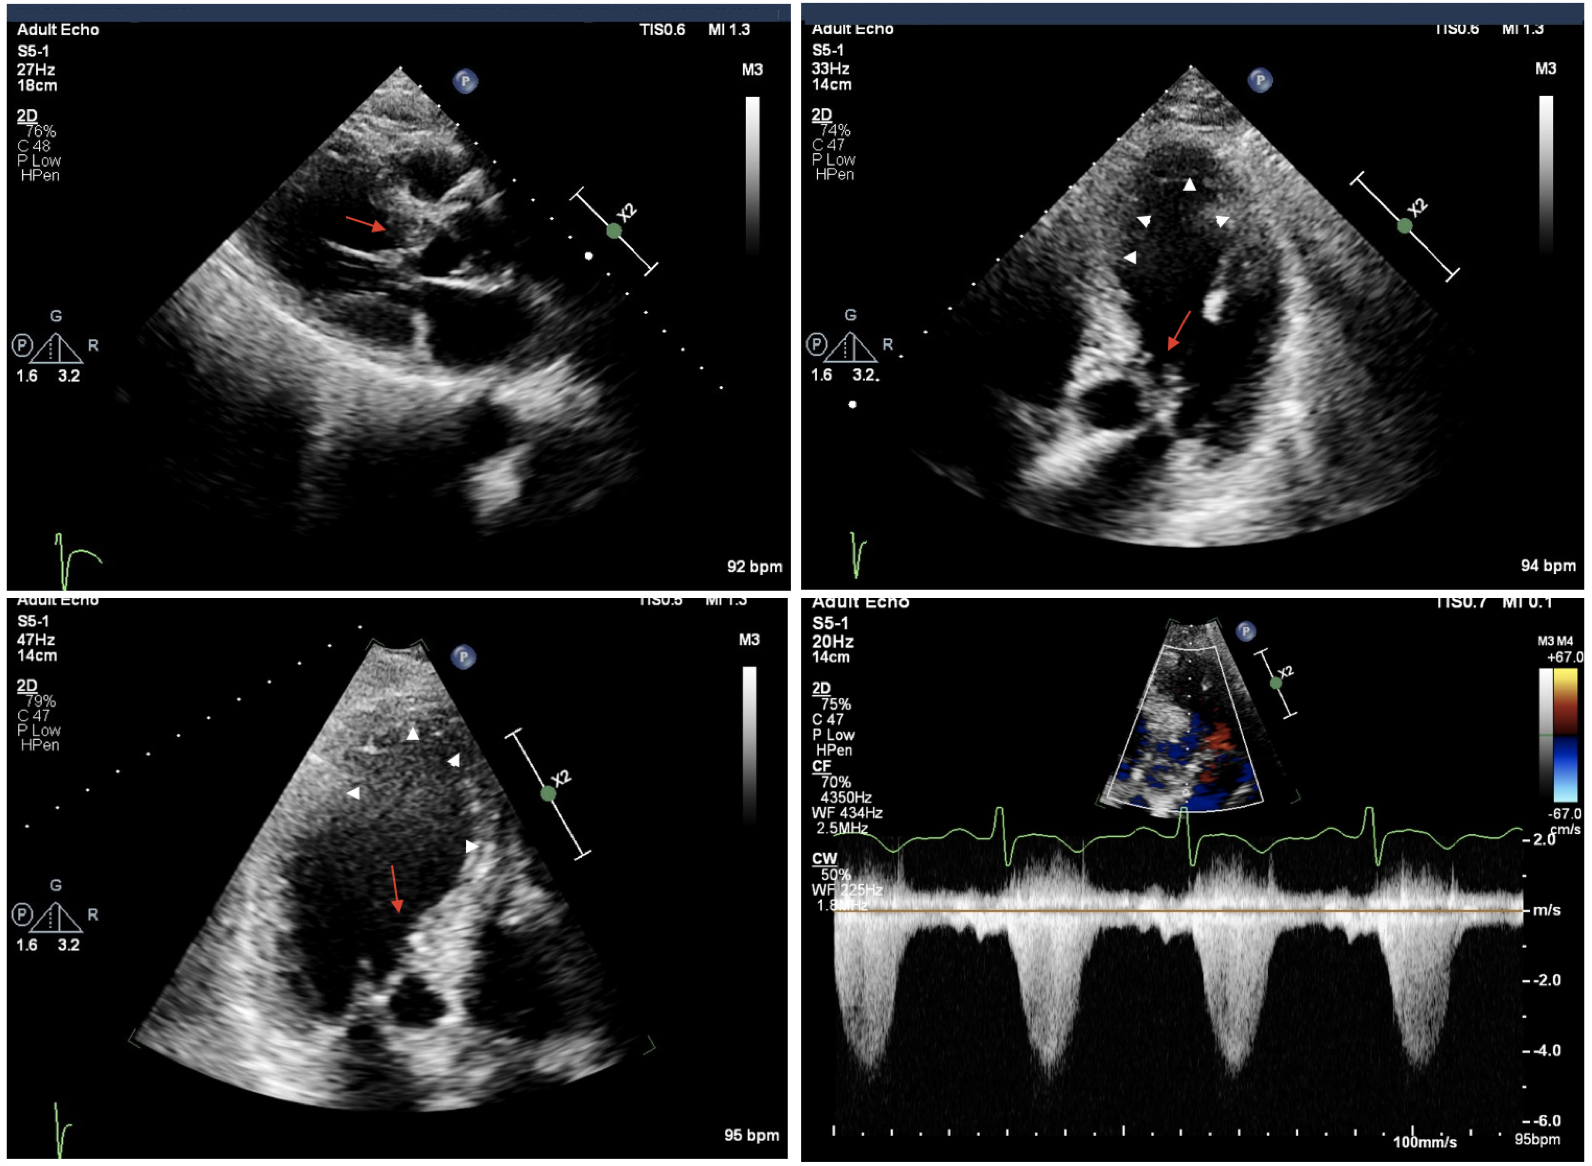

Transthoracic echocardiography in the same patient after access to the ED for chest pain, dyspnea, and unstable hemodynamic condition (blood pressure = 70/40 mm Hg). Parasternal and apical long-axis views and apical 4-chamber views showing acute LV ballooning (white arrowheads) with severe SAM and mitral-septal contact (red arrows). Lower right panel is a continuous-wave Doppler showing high LVOT gradient of 90 mm Hg. Complete recovery after intravenous beta-blocker and phenylephrine infusion was observed. Source: NYU Langone Health